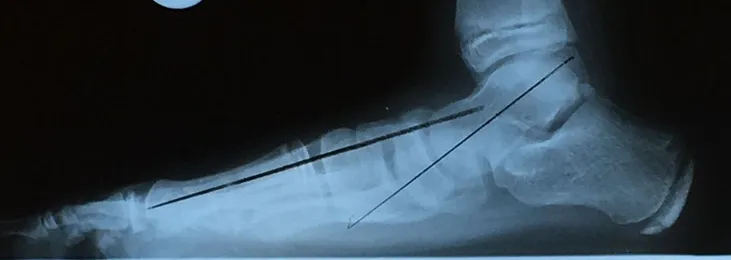

Pre and Postop X-rays Subtalar Joint Implant (Below)

Patient JD

Pre and Postop Subtalar Implant and Percutaneous Achilles Lengthening Below. The first pics show wedging of the distal tibia physis causing ankle valgus due to constant pressure caused by the severity of the flatfoot (JT)